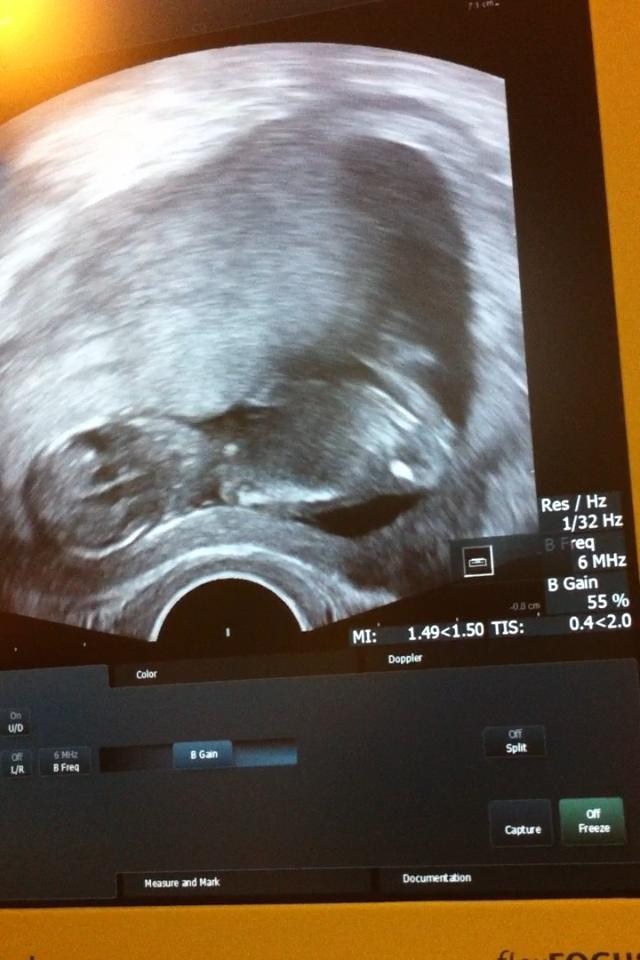

Jeg var til kontrol tjek på Næstved Sygehus igår og blev selvfølgelig scannet igen og cysten jeg har er blevet mindre, ikke meget, men lidt.. så det jo godt nok. Bebs vokser derud af og bokser og sparker hele tiden så det var svært for lægen at få et billed - så han opgav til sidst.. Tilgengæld valgte jeg at optage på video så jeg kunne nyde sparkene på film.. Og så tog jeg lidt billeder ud fra videoen af - men de blev slet, slet ikke gode..

Tilgengæld blev jeg rykket frem. så istedet for at jeg var 11+5(igår) så var jeg 12+2 og bebs målte 55,4 mm.

lige et billed (beklager kvaliteten igen, det som sagt taget udfra en video.